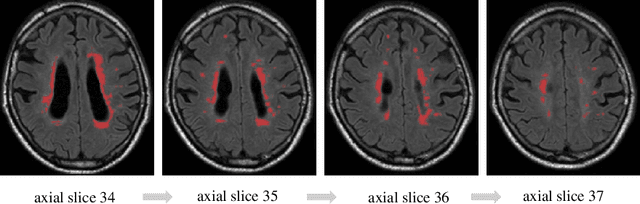

Abstract:Segmentation of both large and small white matter hyperintensities/lesions in brain MR images is a challenging task which has drawn much attention in recent years. We propose a multi-scale aggregation model framework to deal with volume-varied lesions. Firstly, we present a specifically-designed network for small lesion segmentation called Stack-Net, in which multiple convolutional layers are connected, aiming to preserve rich local spatial information of small lesions before the sub-sampling layer. Secondly, we aggregate multi-scale Stack-Nets with different receptive fields to learn multi-scale contextual information of both large and small lesions. Our model is evaluated on recent MICCAI WMH Challenge Dataset and outperforms the state-of-the-art on lesion recall and lesion F1-score under 5-fold cross validation. In addition, we further test our pre-trained models on a Multiple Sclerosis lesion dataset with 30 subjects under cross-center evaluation. Results show that the aggregation model is effective in learning multi-scale spatial information.